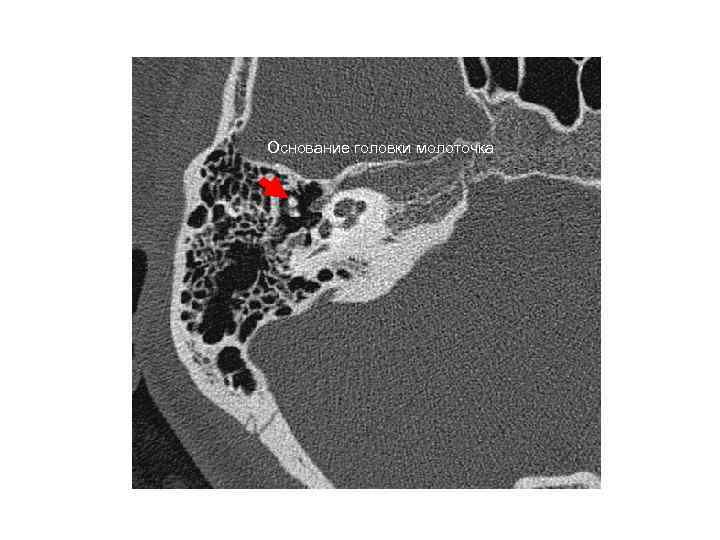

Основание головки молоточка Основание головки молоточка